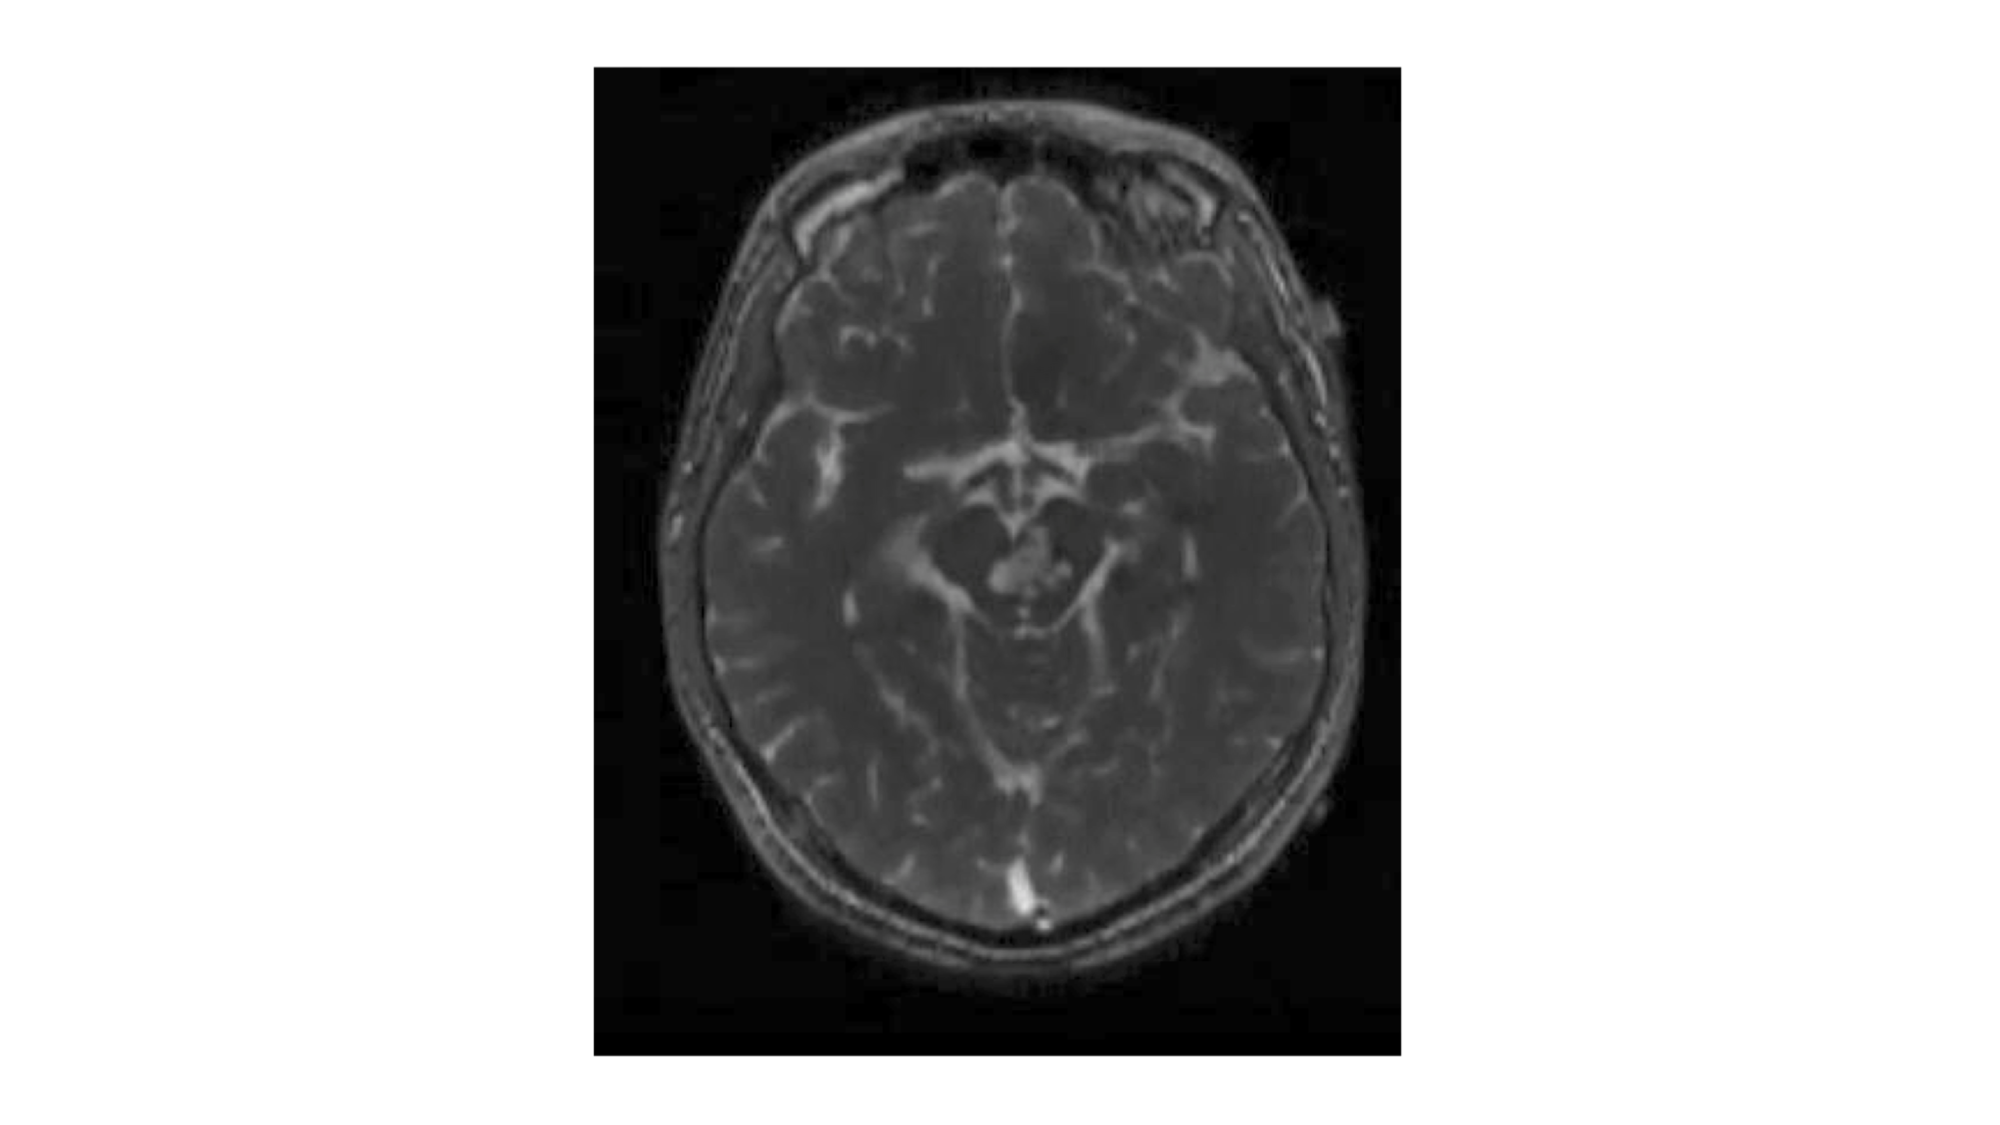

An 18-year-old male presented in 2009 with a six-year history of repeated hemorrhage from a brainstem cavernous malformation (Figure 5).

At his most recent presentation, he developed repeated episodes of temporary right hemiparesis and decreased fluency of speech. The lesion was removed via a lateral brain stem approach. The brain stem was opened using the midbrain entry site along the posterior half of the incision shown in Figure 4. The postoperative magnetic resonance imaging (MRI) of the case illustration is shown in Figure 6.